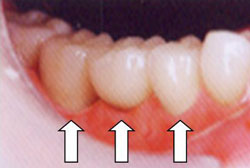

・歯茎のメラニン色素による変色の改善処置

麻酔をして、レーザーメスで歯茎の表面を一層焼き取ることによって、歯茎をきれいなピンク色に戻します。

痛みは麻酔時のみで処置中は痛みはありません。

麻酔が覚めた後は、さわると少し痛い程度で、痛み止めは必要ありません。

一回では綺麗にならないので、同じ場所を2〜3回焼き取る必要があります。完了までの期間:およそ1ヶ月